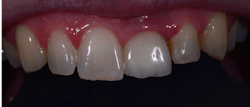

Figure 10: Patient B presented for esthetic concerns about the two centrals. I always make a photo with the lips framing the smile; this comes into play after the dentistry has been performed (figure 12).

Figure 12: Patient B after the central incisors were restored: Often, the patient’s lip line will rise higher following an esthetic improvement. Showing potential patients this type of photograph—with lips—makes a bigger impact than a retracted photo.